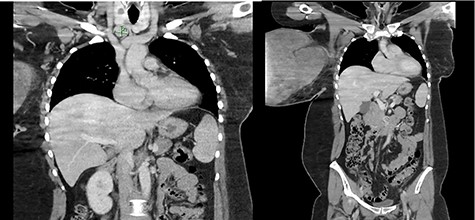

The right breast mass with two ulcerating wounds at centre, stretched-out erythematous skin.

On physical examination, the right breast measured 31 × 23 cm with two well-circumscribed ulcerating wounds over the tumour, which were clinically infected (Fig. 1). On palpation, the right breast was hard and there was palpable ipsilateral axillary lymphadenopathy. The left breast examination was unremarkable.